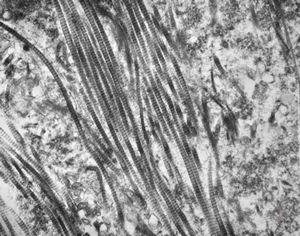

M, 58y. | neurofibroma

M, 58y. | neurofibroma

M, 58y. | neurofibroma